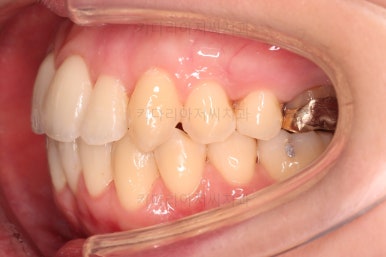

초진 시, 입안의 모습입니다.

좌측 송곳니가 덧니처럼 튀어나가 있고, 송곳니 옆의 작은 억므니가 안으로 쏙 들어가서 덧니 느낌이 더 강조되어 보이네요.

위아래 앞니가 긴밀하게 겹침이 없는 약간의 개방교합(오픈바이트, Openbite) 경향이 보입니다.

옆모습에서 약간의 돌출감이 있으나 힘을 줘서 다물만큼 부자연스러운 양상은 아니여서 돌출에 관해서는 환자분의 취향에 맡기기로 했습니다.